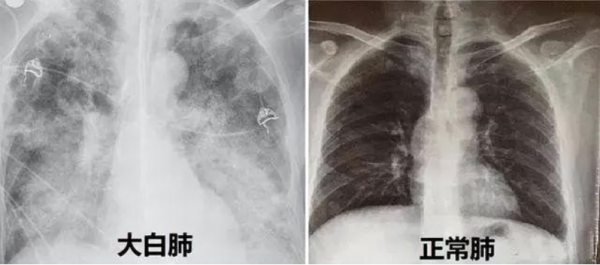

“患者入院时,我们给他做了详细的检查,发现老人的血氧饱和度只有70%,呼吸频率增快约30次/分,CT检查双肺呈现毛玻璃样影,病灶边缘模糊不清,双肺呈现‘白肺’状态,血气分析提示呼吸衰竭,病情十分危重。”91短视频

(南华大学附属长沙中心医院)全科医学科主任、主任医师张辉容介绍,正常人的血氧饱和度通常在95%到100%之间,当下降到90%以下,人体可能因大脑氧气不足而出现昏睡,低于80%则可能对重要器官造成损害,甚至会直接导致窒息、休克、死亡等悲剧的发生。像张爷爷这种情况已经非常危急,幸好护士的电话随访给他争取了抢救治疗的时间,后续医护人员对老人进行了呼吸机辅助呼吸、俯卧位通气、抗感染、营养治疗、肺康复等综合救治,老人的病情开始好转,成功撤掉呼吸机,“白肺”开始吸收,血氧饱和度逐渐恢复到95%以上。

(图片来源网络)

“CT影像检查显示白肺,说明肺炎病变范围较广,甚至几乎累及整个肺部,老人已经发生呼吸衰竭,严重时甚至会出现急性呼吸窘迫综合征。”张辉容主任介绍,肺部是由肺泡组成的,肺泡里边充满了空气,在CT检查时,它通常显示为灰黑色。由于感染、创伤各种原因导致的肺泡里出现炎症,或者感染有渗出液时,肺泡就被这些渗出液或者炎性细胞所填充,有很多沉积物、甚至实变,肺部透过X线的能力大幅减弱,在胸片或者CT上,会看到肺的整个组织不是灰黑色,而是白色,就是大家通常说的“白肺”,这类情况死亡率较高。但白肺是可以预警的,及时发现缺氧状况,及时救治是关键。